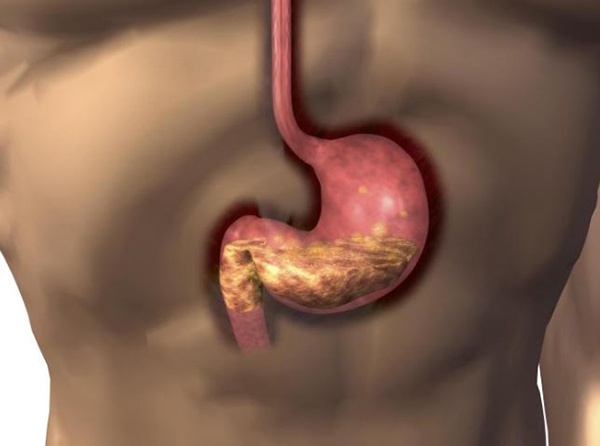

위궤양은 위내막이 손상되거나 염증이 생겨 위산과 소화액이 손상된 부위에 직접 접촉해 발생하는 속상한 질병입니다.

이러한 위궤양은 과도한 스트레스, 폭식, 흡연, 과음, 알코올 섭취, 날카로운 음식을 섭취하는 습관 등이 원인이 될 수 있습니다.